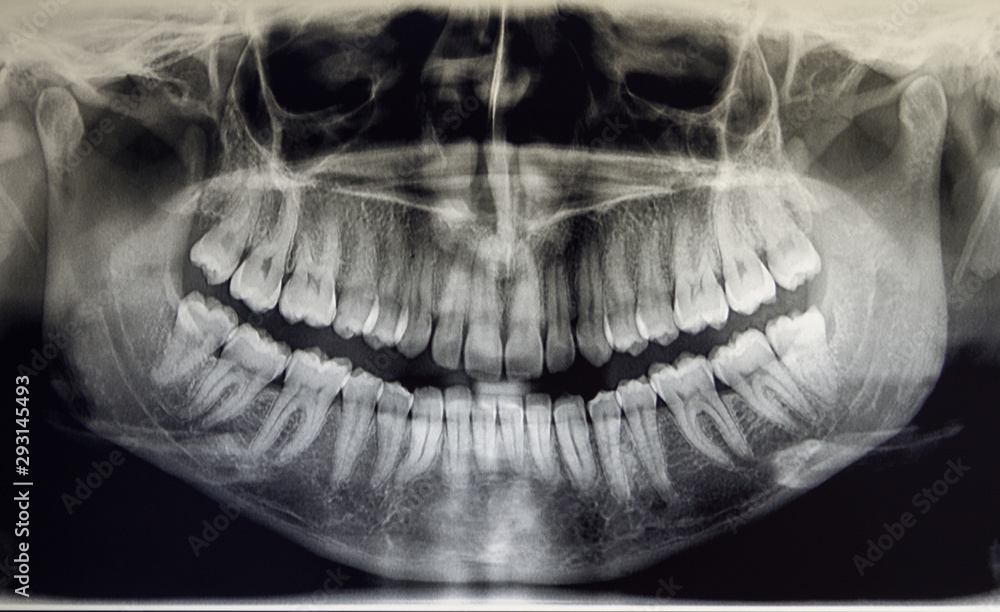

PANTOMOGRAM I CEFALOMETRIA

Zdjęcie pantomograficzne czyli panorama wszystkich zębów, to zdjęcie rentgenowskie, którego obraz obejmuje nie tylko wszystkie zęby ale również, zatoki oraz kanały nerwów.